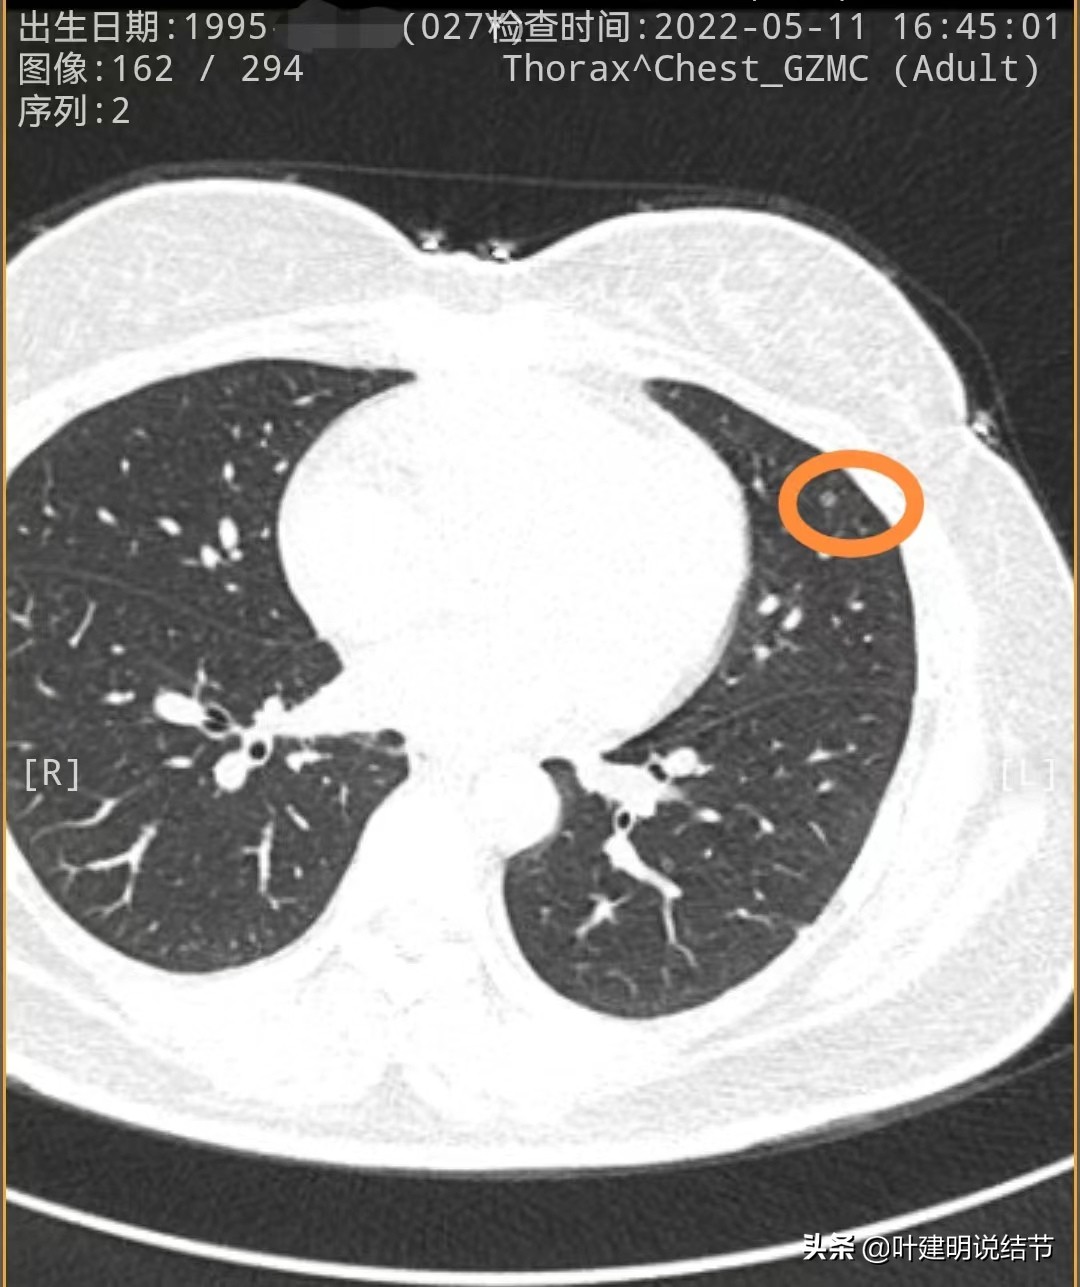

先来看2020年时的CT图像:

左下叶淡磨玻璃结节,轮廓较清,没有实性成分,以不典型增生可能性为大些

左上叶舌段密度偏高结节,边界较清,原位癌可能,也可以是良性结节,边缘膨胀性略差

左下叶另一结节,密度低,轮廓 也清,考虑腺体胶驱病变,不典型增生或原位癌可能性大些

再来看今年2022年的片子:

左下第一处结节几乎没有明显变化

左上舌段结节感觉略圆起来一点,但大小说不上显著增大进展,轮廓清

左下另一处结节感觉略有进展,但总体应该仍是原位癌可能性大些。